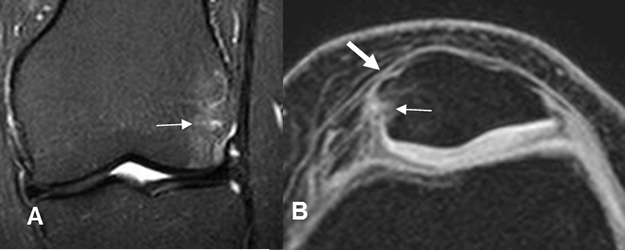

Fig 57 A. Adelgazamiento del retináculo.

A: RM coronal en STIR y B: RM axial en 3D T1 STIR. Contusión femoropatelar, por luxación. (Flechas delgadas).

Cambios inflamatorios en los tejidos blandos y adelgazamiento del retináculo medial, por ruptura parcial. (Flecha gruesa).

Fig 57 B. Ruptura del retináculo.

A: RM coronal en STIR y B: RM axial en FFE T1 STIR. Contusión del cóndilo lateral y el borde interno de la patela. (Flechas delgadas). Hay ruptura del retináculo medial. (Flecha gruesa).